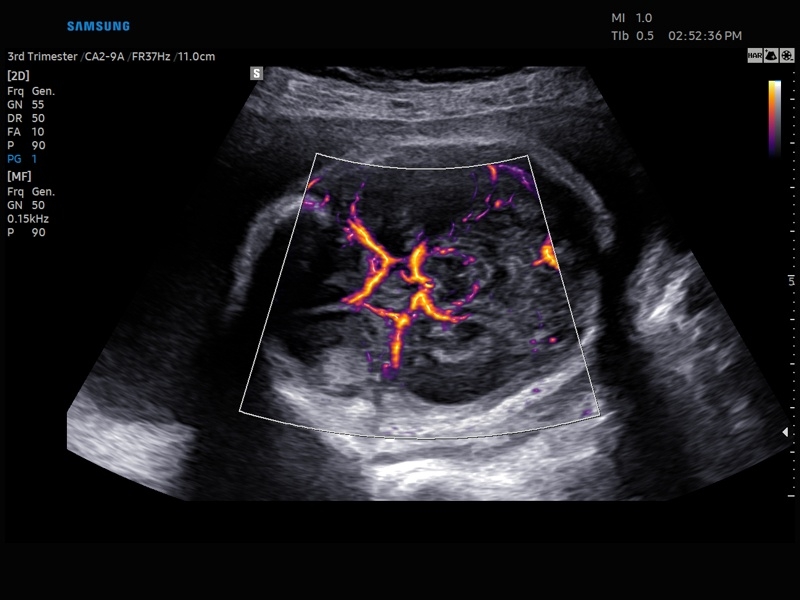

• Модуль MV-Flow – программа (режим), позволяющая визуализировать кровоток в микроциркуляторном русле с высоким разрешением без использования контраста.

• Модуль MV-Flow - программа (режим), позволяющая визуализировать кровоток в микроциркуляторном русле с высоким разрешением без использования контраста.